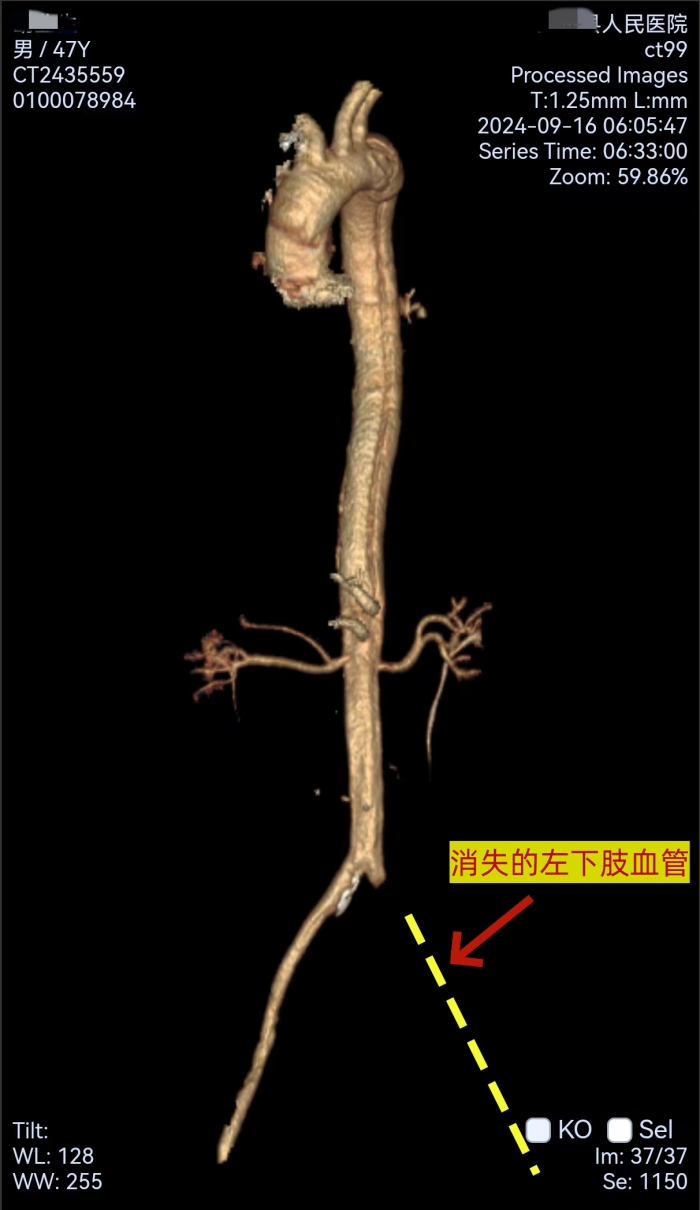

(图片2:术中造影左髂动脉闭塞、右髂动脉真腔细小,从上往下找到真腔)

然而,面对如此严峻的挑战,南溪山医院心脏大血管外科的医疗团队并没有退缩。他们迅速为胡某安排了紧急手术。手术中发现,胡某的病情比发病时更为严重。术中造影显示,其主动脉夹层真腔十分细小,左侧髂总动脉闭塞,右侧髂动脉以假腔供血为主。这一情况给手术带来了巨大的困难。

然而,医生们并未退缩,他们凭借着丰富的经验和精湛的技术,另辟蹊径,从上往下成功找到真腔,并顺利完成了手术。在胸主动脉近端置入覆膜支架一枚,覆盖内膜破口;开通闭塞的左髂总动脉并置入支架;右髂动脉细小真腔内也成功置入支架。手术成功封堵住主动脉内膜破口并恢复下肢供血,挽救了胡某的生命并保住了他的下肢。